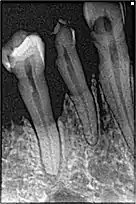

La perte osseuse chez un fumeur

- tabac : facteur de risque majeur. Le tabac, en entraînant une mauvaise vascularisation de la gencive, va énormément influencer l'apparition des premières lésions en diminuant les défenses immunitaires. La consommation du tabac intervient sur la prévalence et la sévérité des parodontites de l'adulte, ainsi que sur les parodontites réfractaires et la gingivite ulcéronécrotique[6],[18],